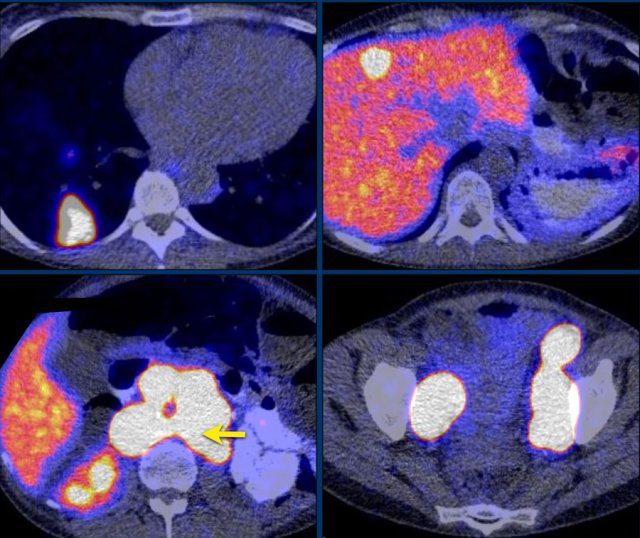

Axial venous phase CT in mediastinal and bone window setting Axial venous phase CT in mediastinal and bone window setting

Images depict mediastinal and bone window setting of a patient with a bulky heterogeneously enhancing right adrenal tumor.

This was proven to be an adrenocortical carcinoma.

There is a faint, ill-defined liver lesion in segment 6 and there are non-specific sclerotic changes in the body of T12.

Continue with the PET-image...

PET-CT performed for complete staging shows intense uptake in the adrenal tumor, indicative of its malignant nature.

There is also intense uptake in two liver metastases and in a bone metastasis in T12.

Approximately 20-40% of patients with an adrenocortical carcinoma present with metastases at diagnosis.

Whole-body FDG PET-CT can distinguish benign from malignant lesions with high sensitivity (100%), but with lower specificity (87- 97%).